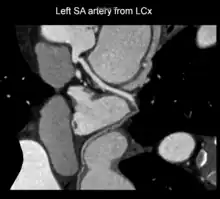

Curved planar reformatted image of sinoatrial nodal artery originating from proximal left circumflex artery. Variant anatomy.

A left S-shaped sinoatrial artery, originating from the proximal left circumflex or LCx artery, has been described as a common variant in approximately 10% of human hearts.[5] This artery is larger than normal and supplies a good part of the left atrium, but also right-sided structures like part of the sinoatrial node and the atrioventricular nodal areas. In this variant, the artery courses in the sulcus between the left superior pulmonary vein and the left atrial appendage where it could be susceptible to injury during catheter or surgical ablation procedures on the left atrium, especially for atrial fibrillation ablation or open-heart cardiac surgery.